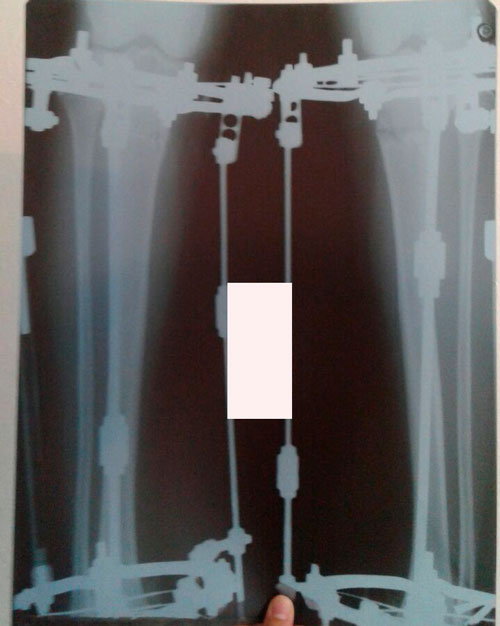

Рентген в 60 дней

Пора на снятие аппаратов!